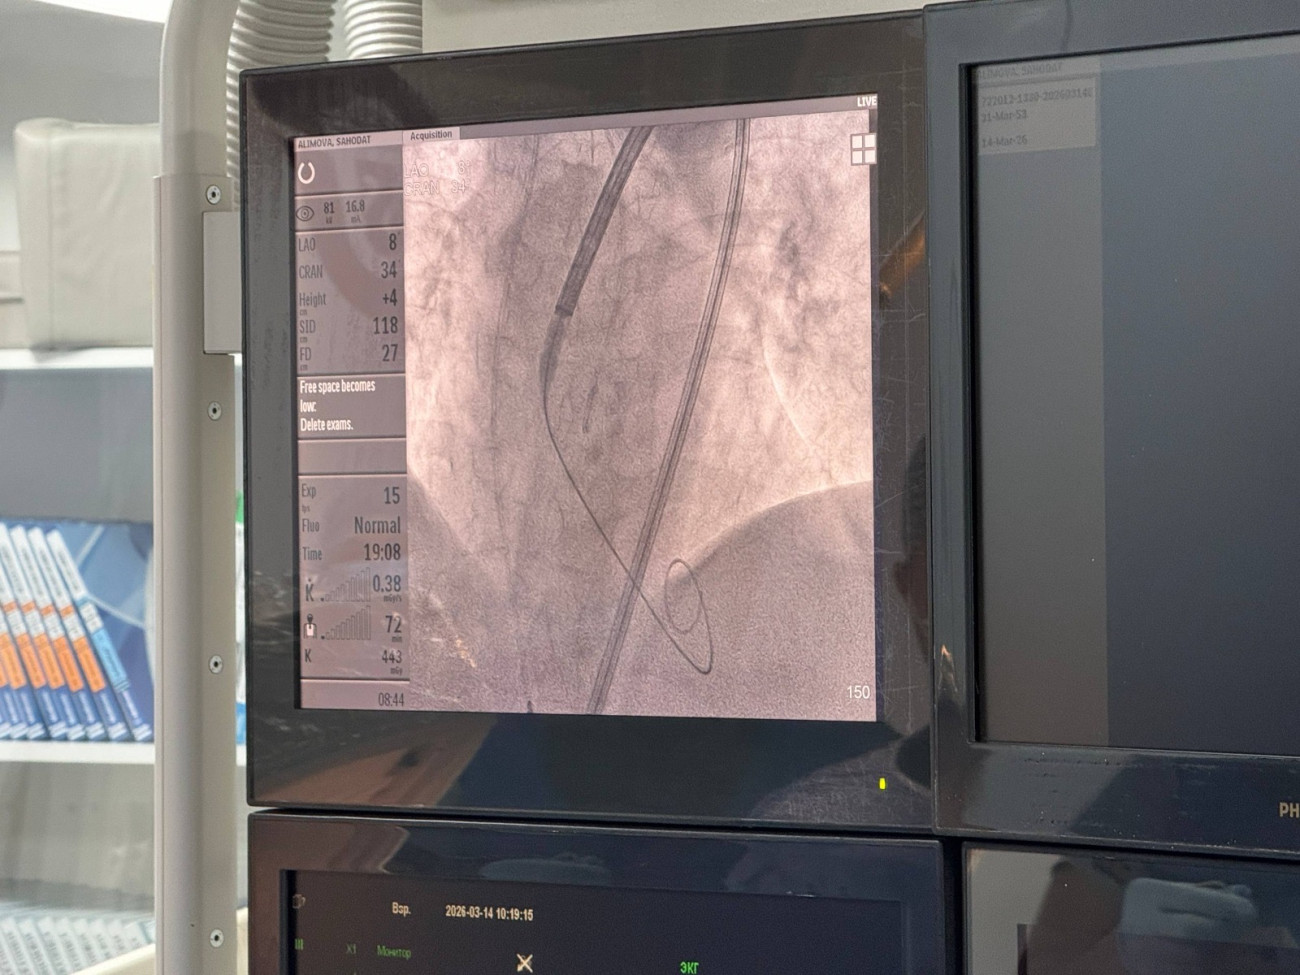

Bir tıp kliniğinde 72 yaşındaki bir hastaya modern TAVI operasyonu (transkateter aort kapak implantasyonu) başarıyla gerçekleştirildi. Büyük cerrahi kesiler yapılmadan uygulanan bu yöntem klinikte ilk kez kullanıldı.

Yaklaşık on yıldır kalp hastalığıyla mücadele eden hastanın durumu son yıllarda damar daralması nedeniyle ağırlaşmıştı. Operasyon sırasında bacak damarından ince bir kateter yerleştirilerek kalbe yeni bir aort kapağı takıldı. Yaklaşık bir buçuk saat süren ameliyat başarıyla tamamlandı.

Ameliyata Rusya’dan gelen uzmanlar ve yerel özel kliniklerin doktorları da katıldı. Hastanın şu anda yoğun bakımda doktorların gözetiminde olduğu ve durumunun stabil olduğu bildirildi.